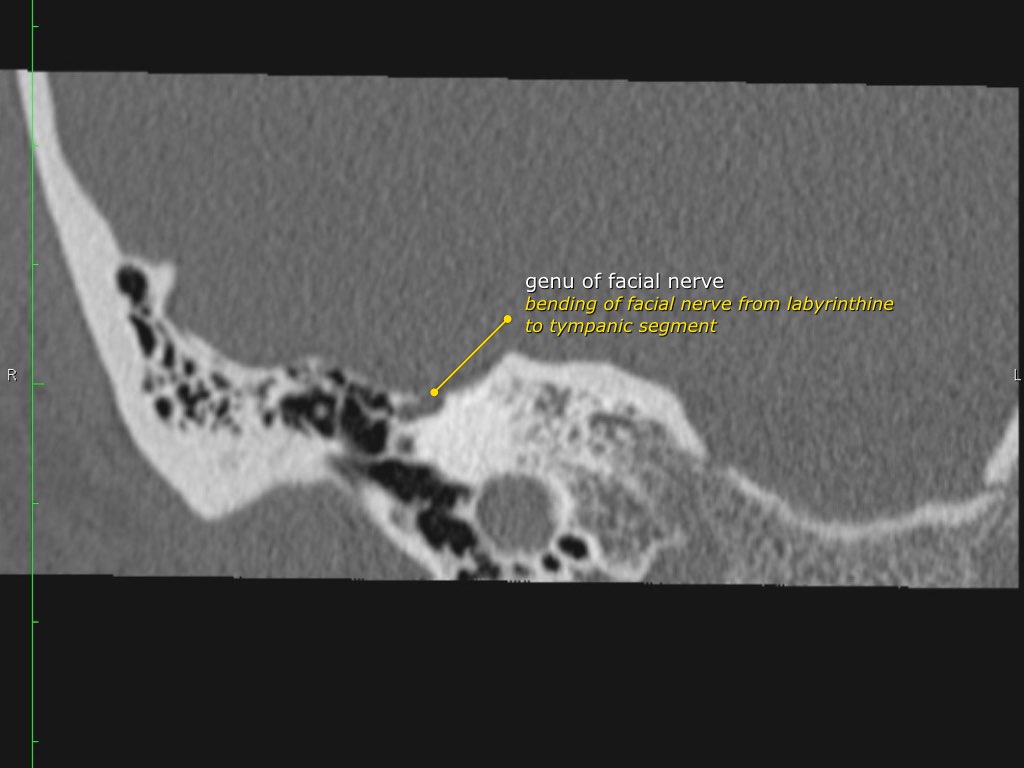

Đoạn mê nhĩ của dây thần kinh mặt xuất phát từ ống tai trong, chạy gần như vuông góc với trục dài của xương đá, gập góc nhọn về phía trước để đến hạch gối (geniculate ganglion).

Tại hạch gối, dây thần kinh mặt tạo thành một khúc quặt hình chữ U (genu thứ nhất của dây thần kinh mặt) để chạy ra phía sau theo đoạn nhĩ dọc theo thành trong của thượng nhĩ.